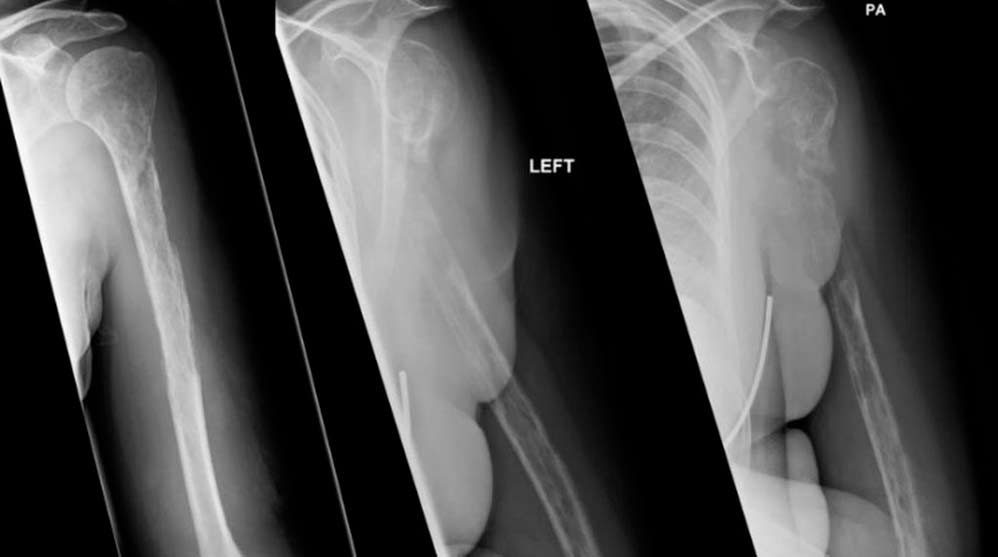

Los huesos se presentan como la base del cuerpo humano, un sistema o mecanismo que basa sus máximas en soportar el peso del cuerpo y permitir al mismo realizar numerosos movimientos. Ahora bien, ¿te imaginas que comienzan a desaparecer los huesos de tu cuerpo? Pues es exactamente lo que le ha ocurrido a una mujer que comenzó a sufrir enormes dolores en el brazo y hombro izquierdos. Después de un tiempo, la paciente decidió acudir al hospital, donde detectaron una lesión tumoral en el húmero. Los médicos pensaron que estos dolores podrían deberse a un claro caso de cáncer de hueso, sin embargo, los análisis posteriores detectaron que el cuerpo de la mujer no poseía ningún tipo de células cancerígenas.

Las pruebas fueron siendo cada vez más habituales y, para sorpresa de los médicos, se dieron cuenta que, tras numerosas radiografías, el húmero y algunos huesos del antebrazo estaban desapareciendo. Sí, los huesos se estaban desvaneciendo cuál terrón de azúcar en un baso de leche. Después de varios días de incesantes pruebas, los médicos se dieron cuenta que la mujer poseía el síndrome de Gorham-Stout, también conocido como el síndrome de los huesos que se desvanecen. Una afección de la que solo existen 62 casos documentados hasta la fecha y de la que se desconoce el origen.